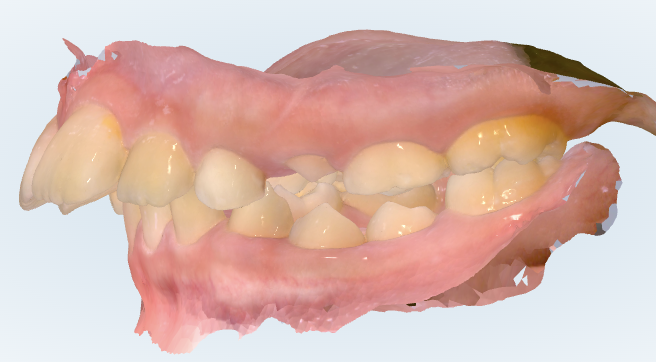

初診時の画像診断

出っ歯の歯並びをしています。

そうですね、実際に拝見すると、前歯の突出(出っ歯傾向)に加えて、奥歯の位置関係も前方にずれている状態です。

また、レントゲンでは、本来生える位置に対して犬歯(3番目の歯)が前方に向かって進んでおり、隣の歯(前から2番目の歯)の根に影響を与えている可能性があります。